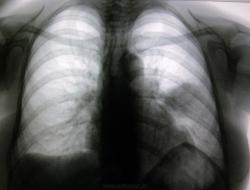

Лечите пневмонию в 6-ке нижней доли левого лёгкого. Потом Р-контроль.

Неоднородное затемнение, как бы не превратилось в полость.Левый корень широк.Но все равно хорошо лечить и контроль.

подозреваю, что там формируется полость. Кстати, в заключении я написал "признаки абсцедирующей пневмонии". Но на контроле посмотрим.